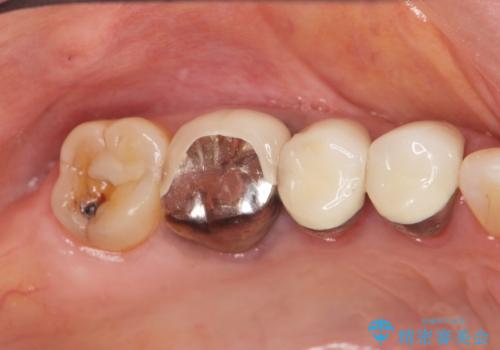

古くなったセラミッククラウンのやりかえ

- 老朽化し黒ずんできたクラウンのやりかえを希望され来院されました。

将来的に歯ぐきの位置が変化しても審美障害となりづらいオールセラミックジルコニアクラウンによるやり替えを計画します。

- 33万円(仮歯・ファイバーコア・ジルコニアクラウン×3)費用は治療当時の料金となります